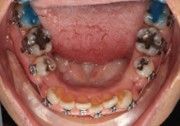

The IOS Mini Cinch Back Plier demonstrated superior control and a significantly reduced risk of bracket debonding and wire deformation compared to the regular Hammerhead plier from a different brand. Wire bends achieved with the IOS Mini Cinch Back Plier maintained integrity even under high-torque activation. The following images illustrate key differences in bend quality, wire distortion, and proximity to the bracket between the IOS Mini Cinch Back Plier and the conventional Hammerhead plier.